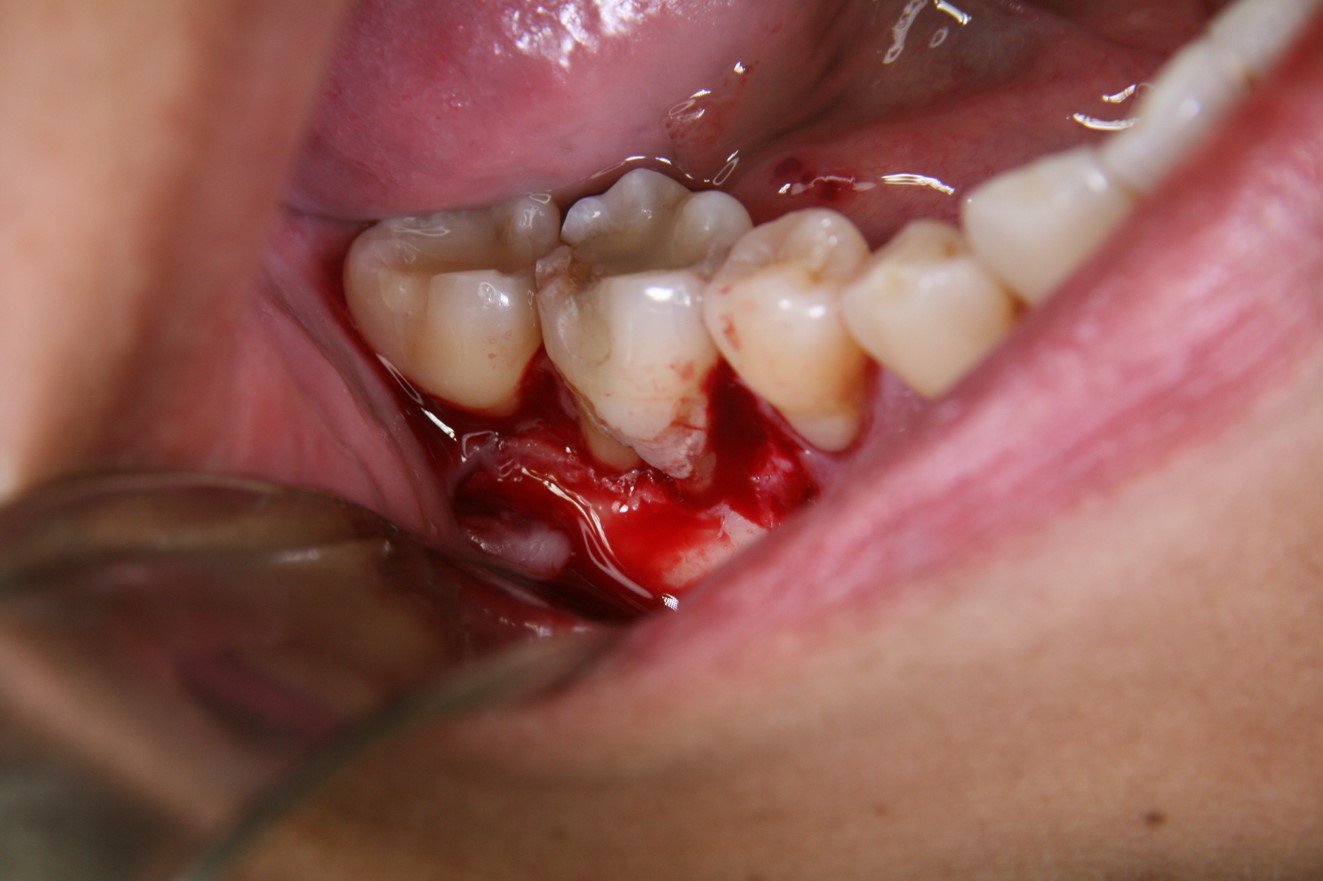

Fig 8. Resorption occurred in the area where the implant was placed, necessitating re-entry, clean-up, and bone grafting.

Figure 8

Fig 9. The soft tissue was released enough to enable placement of the bone grafting material using either a periosteal or index finger.

Figure 9

Fig 10. PLGA alloplast bone grafting material was placed around the implant at No. 8. The material provided between 1 to 2 minutes of working time and molded into shape; once the bone material solidifies, a membrane will be placed and the area closed with the soft tissue.

Figure 10

Fig 11. The alloplast material was molded into shape and placed at the No. 9 site.

Figure 11

Fig 12. Additional alloplast material was placed to fill the defect area.

Figure 12

Fig 13. Once the desired shape was achieved and the alloplast material had hardened, a membrane was placed so soft-tissue closure could be performed.

Figure 13